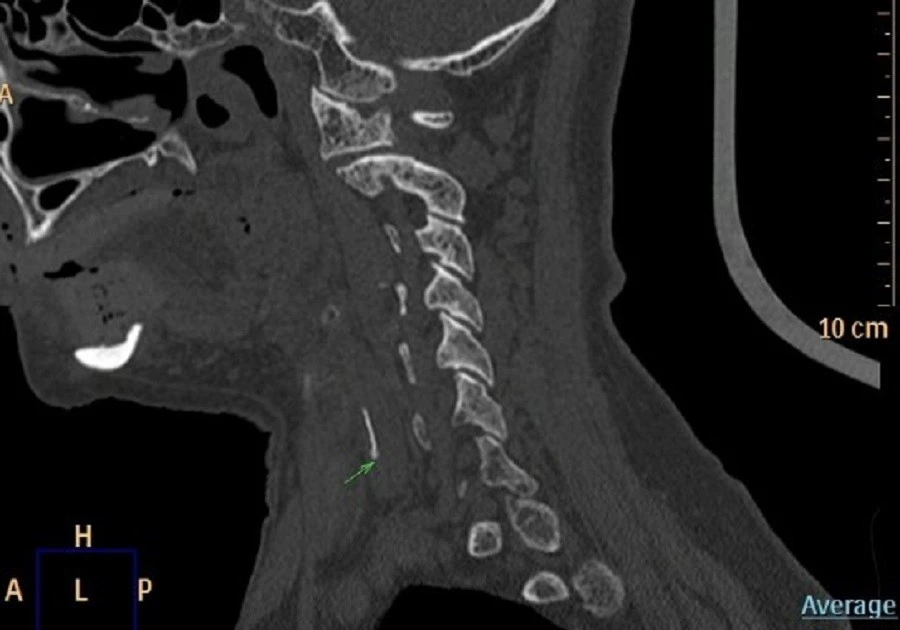

Sau vài ngày, cảm giác đau và vướng không giảm mà ngày càng nặng, khiến việc ăn uống trở nên khó khăn. Khi đến khám, nội soi Tai Mũi Họng phát hiện phù nề nghiêm trọng ở vùng sụn phễu trái. X‑quang cổ nghi ngờ có dị vật và CT xác định một mảnh xương cá khoảng 1×22 mm đã xuyên ra khỏi đường tiêu hóa và cắm sâu vào thùy trái tuyến giáp.